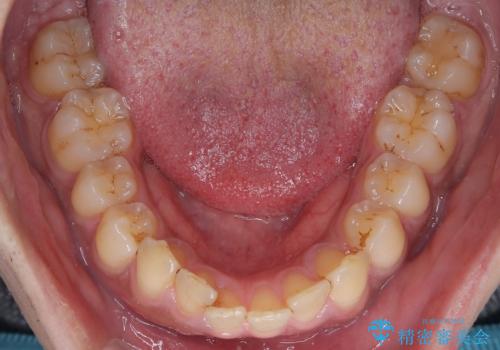

- 上の前歯の正中離開(すきっ歯)と、下顎前歯部の叢生(デコボコ)を主訴に来院された患者様の症例です。

「目立ちにくい装置で治療したい」とのご希望があり、透明のマウスピース矯正であるインビザラインを用いて矯正治療を行いました。